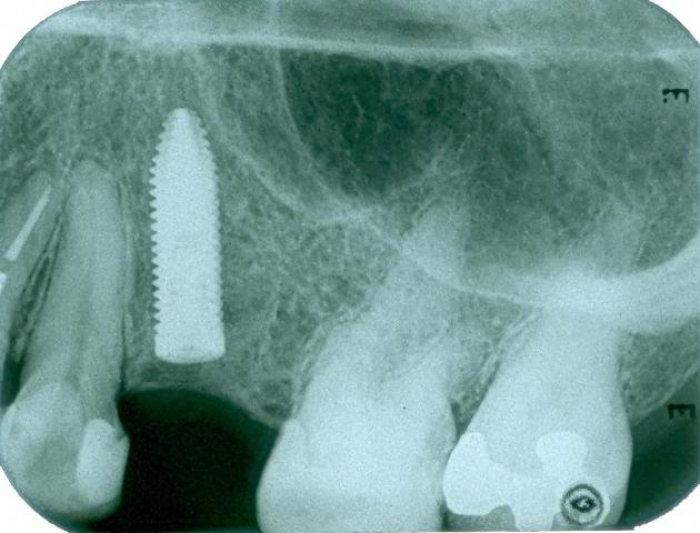

Raio X com implante instalado

Raio X final